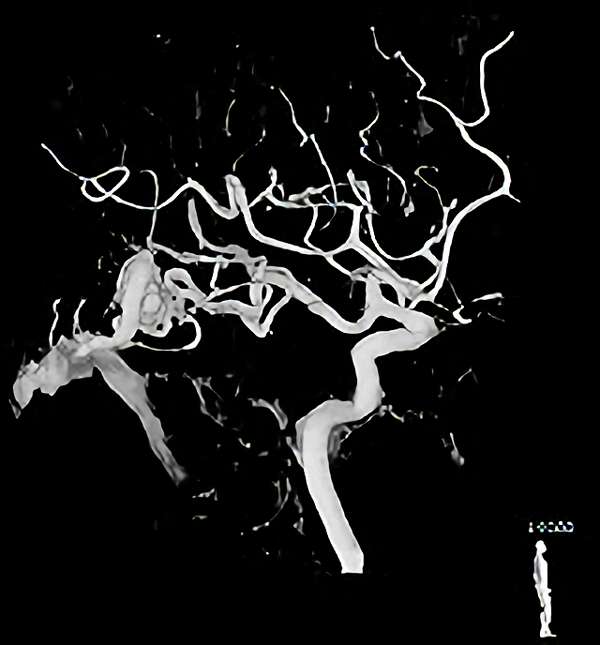

脳血管撮影

手術前

手術後